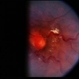

- retinal capillary hemangioblastoma, lipid exudation

- Retinal capillary hemangioblastoma with lipid surrounding.